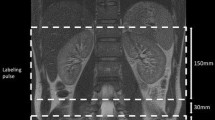

The subjects underwent imaging on a 3-T MRI scanner (Ingenia-CX, Philips Medical Systems) using a 32-element phased-array direct digital radio frequency receiver coil and peripheral pulse unit gating. During the same session, we acquired pulse and navigator echo-gated non-contrast-enhanced MRA using both MSG-EPI and b-SSFP sequences, with 3D imaging performed in the transverse plane. We set the image acquisition to occur during the systole of the peripheral pulse cycle. To obtain a bright blood signal, we applied an inversion pulse with the shortest delay time to the region of interest to enhance the contrast between flowing and static magnetization. This technique has been widely used for renal MRA with b-SSFP [21,22,23,24]. We tried to replicate the study parameters for the two sequences as much as possible; however, we used the water excitation technique (the principle of selective excitation technique, ProSet) for MSG-EPI and the spectral presaturation with inversion recovery (SPIR) for b-SSFP due to limitations of the MR scanner used in this study. Conventional spectrally selective fat suppression techniques cannot provide homogeneous fat suppression within the sampling time. We recorded the acquisition times for the 3D MSG-EPI and b-SSFP sequences.

Figure 1 shows schematics of the 3D MSG-EPI and b-SSFP sequences. The MSG-EPI sequence was similar to single-shot gradient-type EPI, except that several acquisitions were made rather than sampling the k-space completely with one shot. The MSG-EPI sequence allows many signals to be obtained with one radio frequency excitation; however, the signal acquisition time is limited by T2* relaxation. The acquisition of many k-space lines increases echo time and repetition time and results in reduced SNR and blurring. We therefore used an EPI factor of 7, which can yield seven echoes per excitation. The detailed scanning parameters are shown in Table 1.

Commonly, renal non-contrast MRA techniques apply a spatially selective inversion pulse with a long inversion delay to maximize the inflow signal inside the renal arteries. A recent paper reported the effectiveness of background signal suppression by this subtraction method; however, there is a problem of increased imaging time with double imaging and deterioration of image quality due to mis-registration [22]. In this study, we suppressed the background signals effectively by applying an inversion pulse with a short inversion delay rather than a long delay [10] and by using a ProSet pulse for fat suppression. Consequently, we succeeded in depicting the renal arteries with high contrast against the background signals, although this was mostly due to the differences in relaxation times and was independent of inflow effects. Because this technique is less sensitive to flow speed, exact inversion delay settings are not needed. This suggests that the technique can yield more robust results compared with inflow-based methods, regardless of the patient conditions. Furthermore, using a short inversion delay allows the scan time to be kept relatively short, such as for a breath-holding scan, which can result in reduced motion artifacts compared to conventional free-breathing inflow techniques.